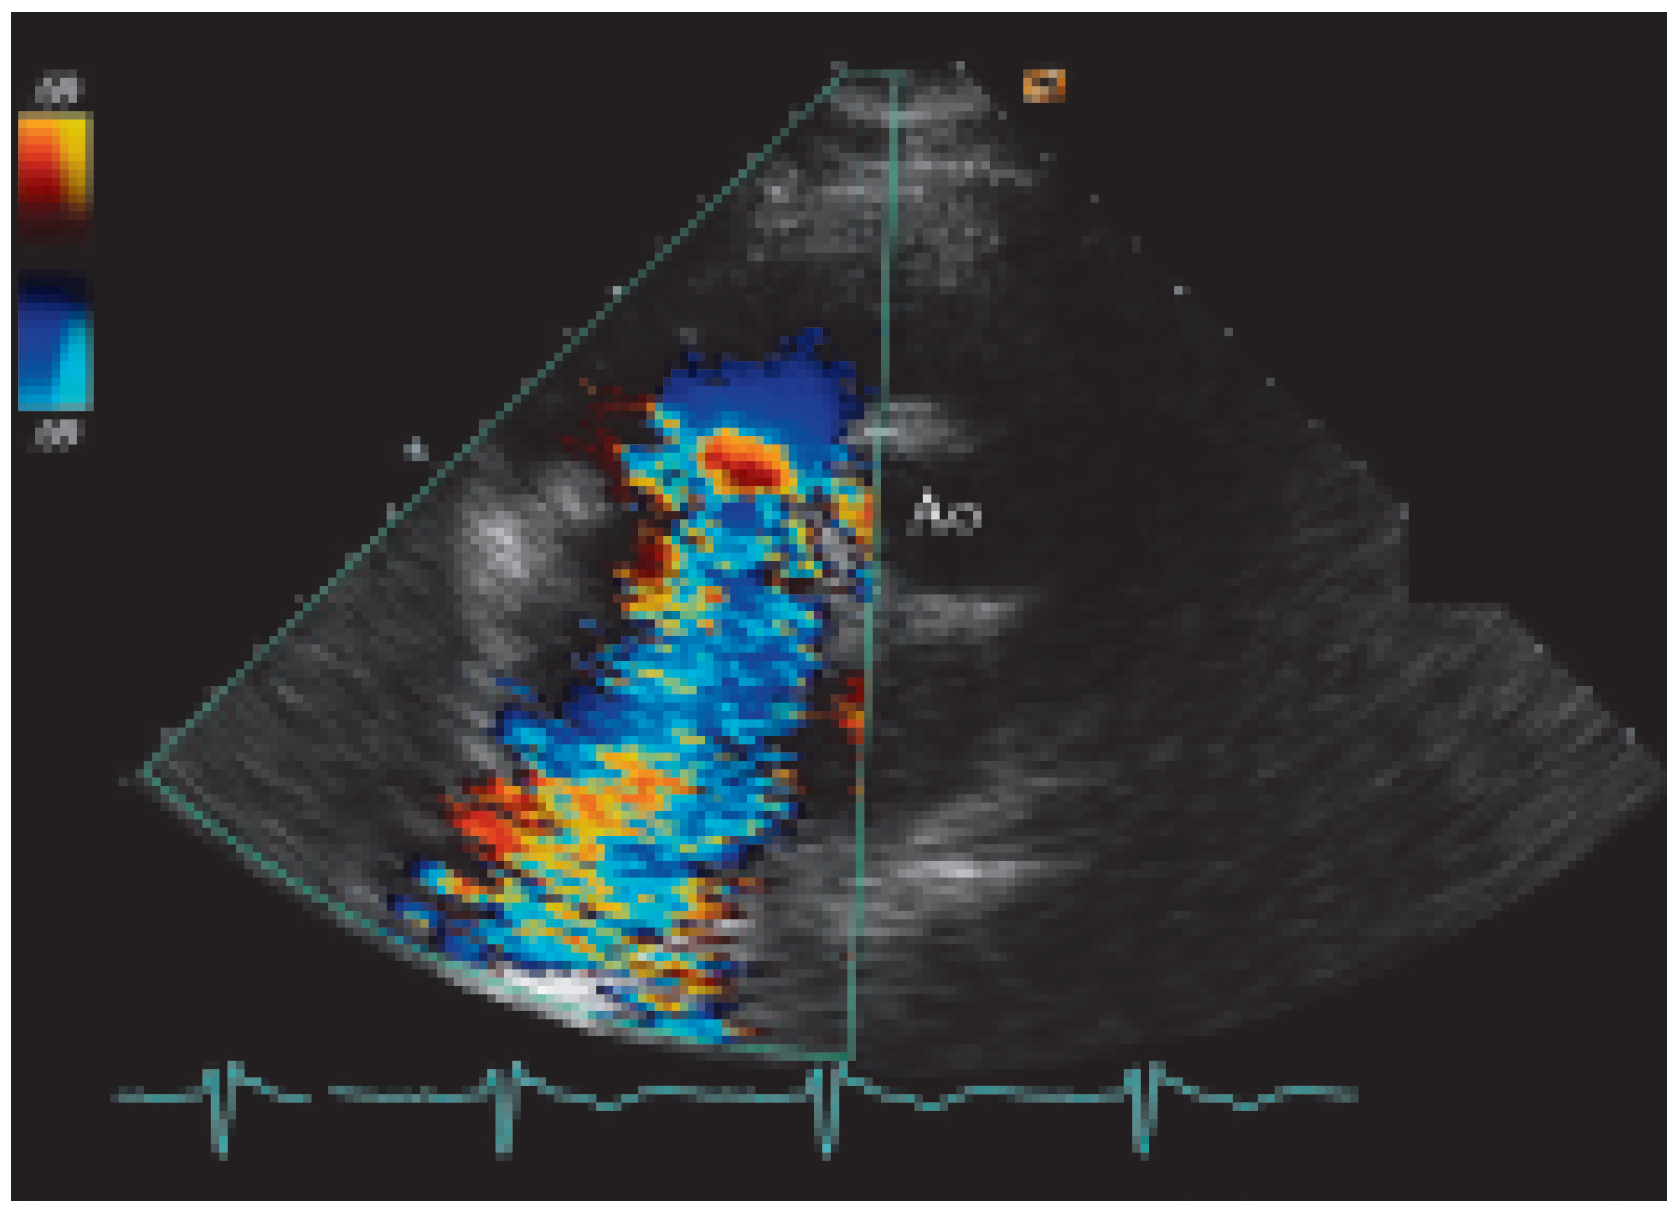

Présentation de cas